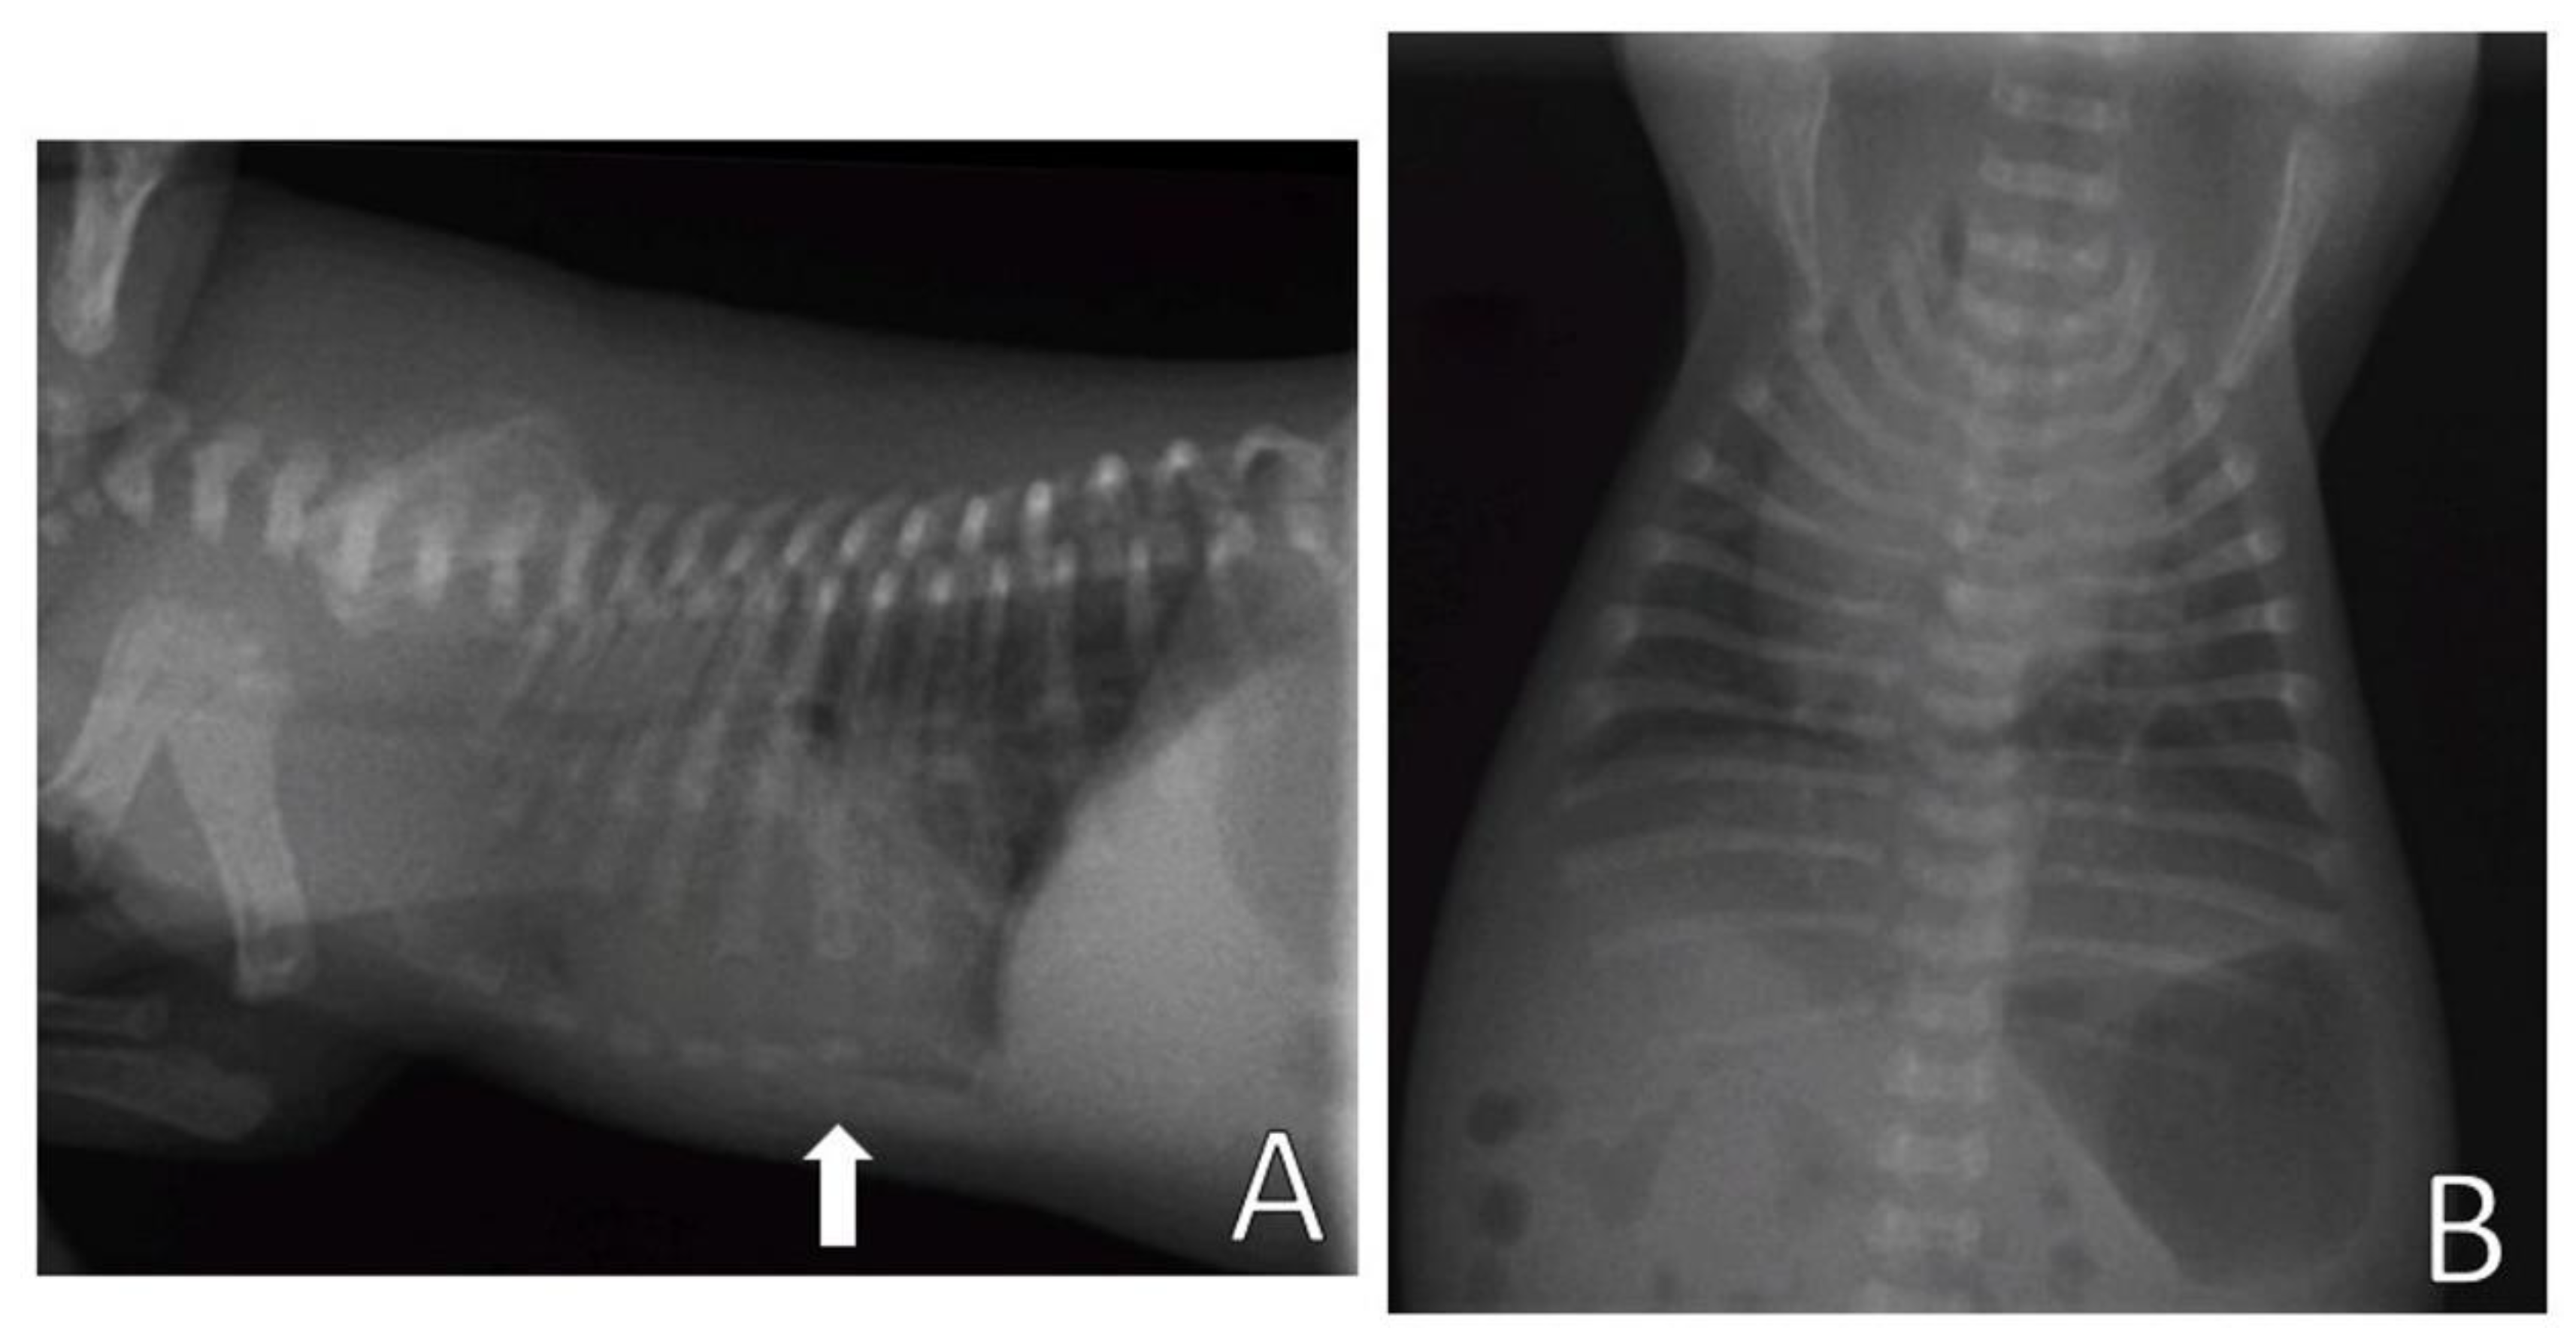

Complementary tests, hemogram and chest X-ray, were performed. Blood (0.4 mL) from the jugular vein was collected for the hemogram, which was within the reference standards for age. The chest X-ray (Figure 11) was performed in the right lateral and ventrodorsal positions, observing a ventrodorsal deviation of the sternum and diagnosing pectus excavatum. The frontosagittal and vertebral indices corresponded to 1.7 cm (≤2 cm) and 10 cm (>9 cm), respectively, classifying the pectus as mild grade. In addition, a rounded cardiac silhouette (globose aspect) and right cardiac deviation were observed.

Figure 11.

Chest X-ray. (A) Right lateral position, demonstrating ventrodorsal deviation of the sternum bone (arrow). (B) Ventrodorsal position, demonstrating rounded cardiac silhouette and right cardiac deviation.